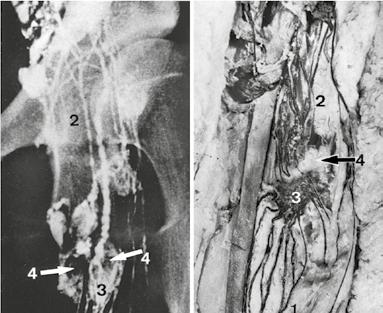

► Obr. 1.17 ukazuje sektorové plnění lymfatické uzliny. Mezery v plnění mohou být v normální uzlině způsobeny například fibrotickými změnami nebo zvětšením uzliny (► obr. 1.17 a). Mezera v plnění může být ale také interpretována jako fyziologický jev, spočívající v internodální lokalizaci periferní oblasti. Jak ukazuje ► obr. 1.18 b, plní kolektory ventromediálního svazku spodní polovinu centrální inguinální uzliny. Mezera v plnění v horní polovině uzliny představuje drenážní oblast aferentních cév stehna, které nejsou plněny ventromediálním svazkem.

Obr. 1.17 a–c Sektorové napojené lymfatické uzliny. a Odvodná lymfatická céva a regionální lymfatické uzliny kůže genitálu (nástřik tuší, člověk); b odvod tuše in vivo (plíce, pes); c schéma plnění uzliny. 1 Aferentní lymfatické cévy; 2 tuší značené sektory v nll. inguinales superomediales; 3 v. saphena magna; 4 centrální inguinální uzlina; 5 členové laterální skupiny řetězce; 6 tuší naplněný segment lobus cardiacus; 7 naplněný sektor v bifurkační uzlině; 8 bifurkace trachey; 9 sektor plnění. [M 124]

Obr. 1.18 Částečné plnění uzlin; mezery v plnění. a Lymfogram inguinálních uzlin; b nástřikový preparát (člověk). 1 Aferentní cévy; 2 eferentní cévy; 3 naplněná oblast uzliny; 4 mezera v plnění. [M 124]